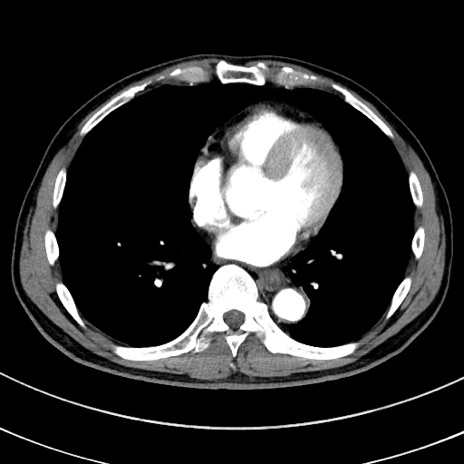

冠状断像

症例8(横断像)

【症例】 60歳代男性

【主訴】 黒色吐物

【現病歴】 4日前から嘔気自覚、2日前の朝食後にも嘔気あり、自分で手で嘔吐反射起こし嘔吐したところ血が混ざっていたため受診。

【既往歴】 5年前汎発性腹膜炎を伴う急性虫垂炎で手術、高血圧、前立腺肥大症、高脂血症

【身体所見】 腹部正中に手術癩痕あり 腹部平坦・軟圧痛なし膨満感あり

【データ】WBC 8400、CRP 4.54